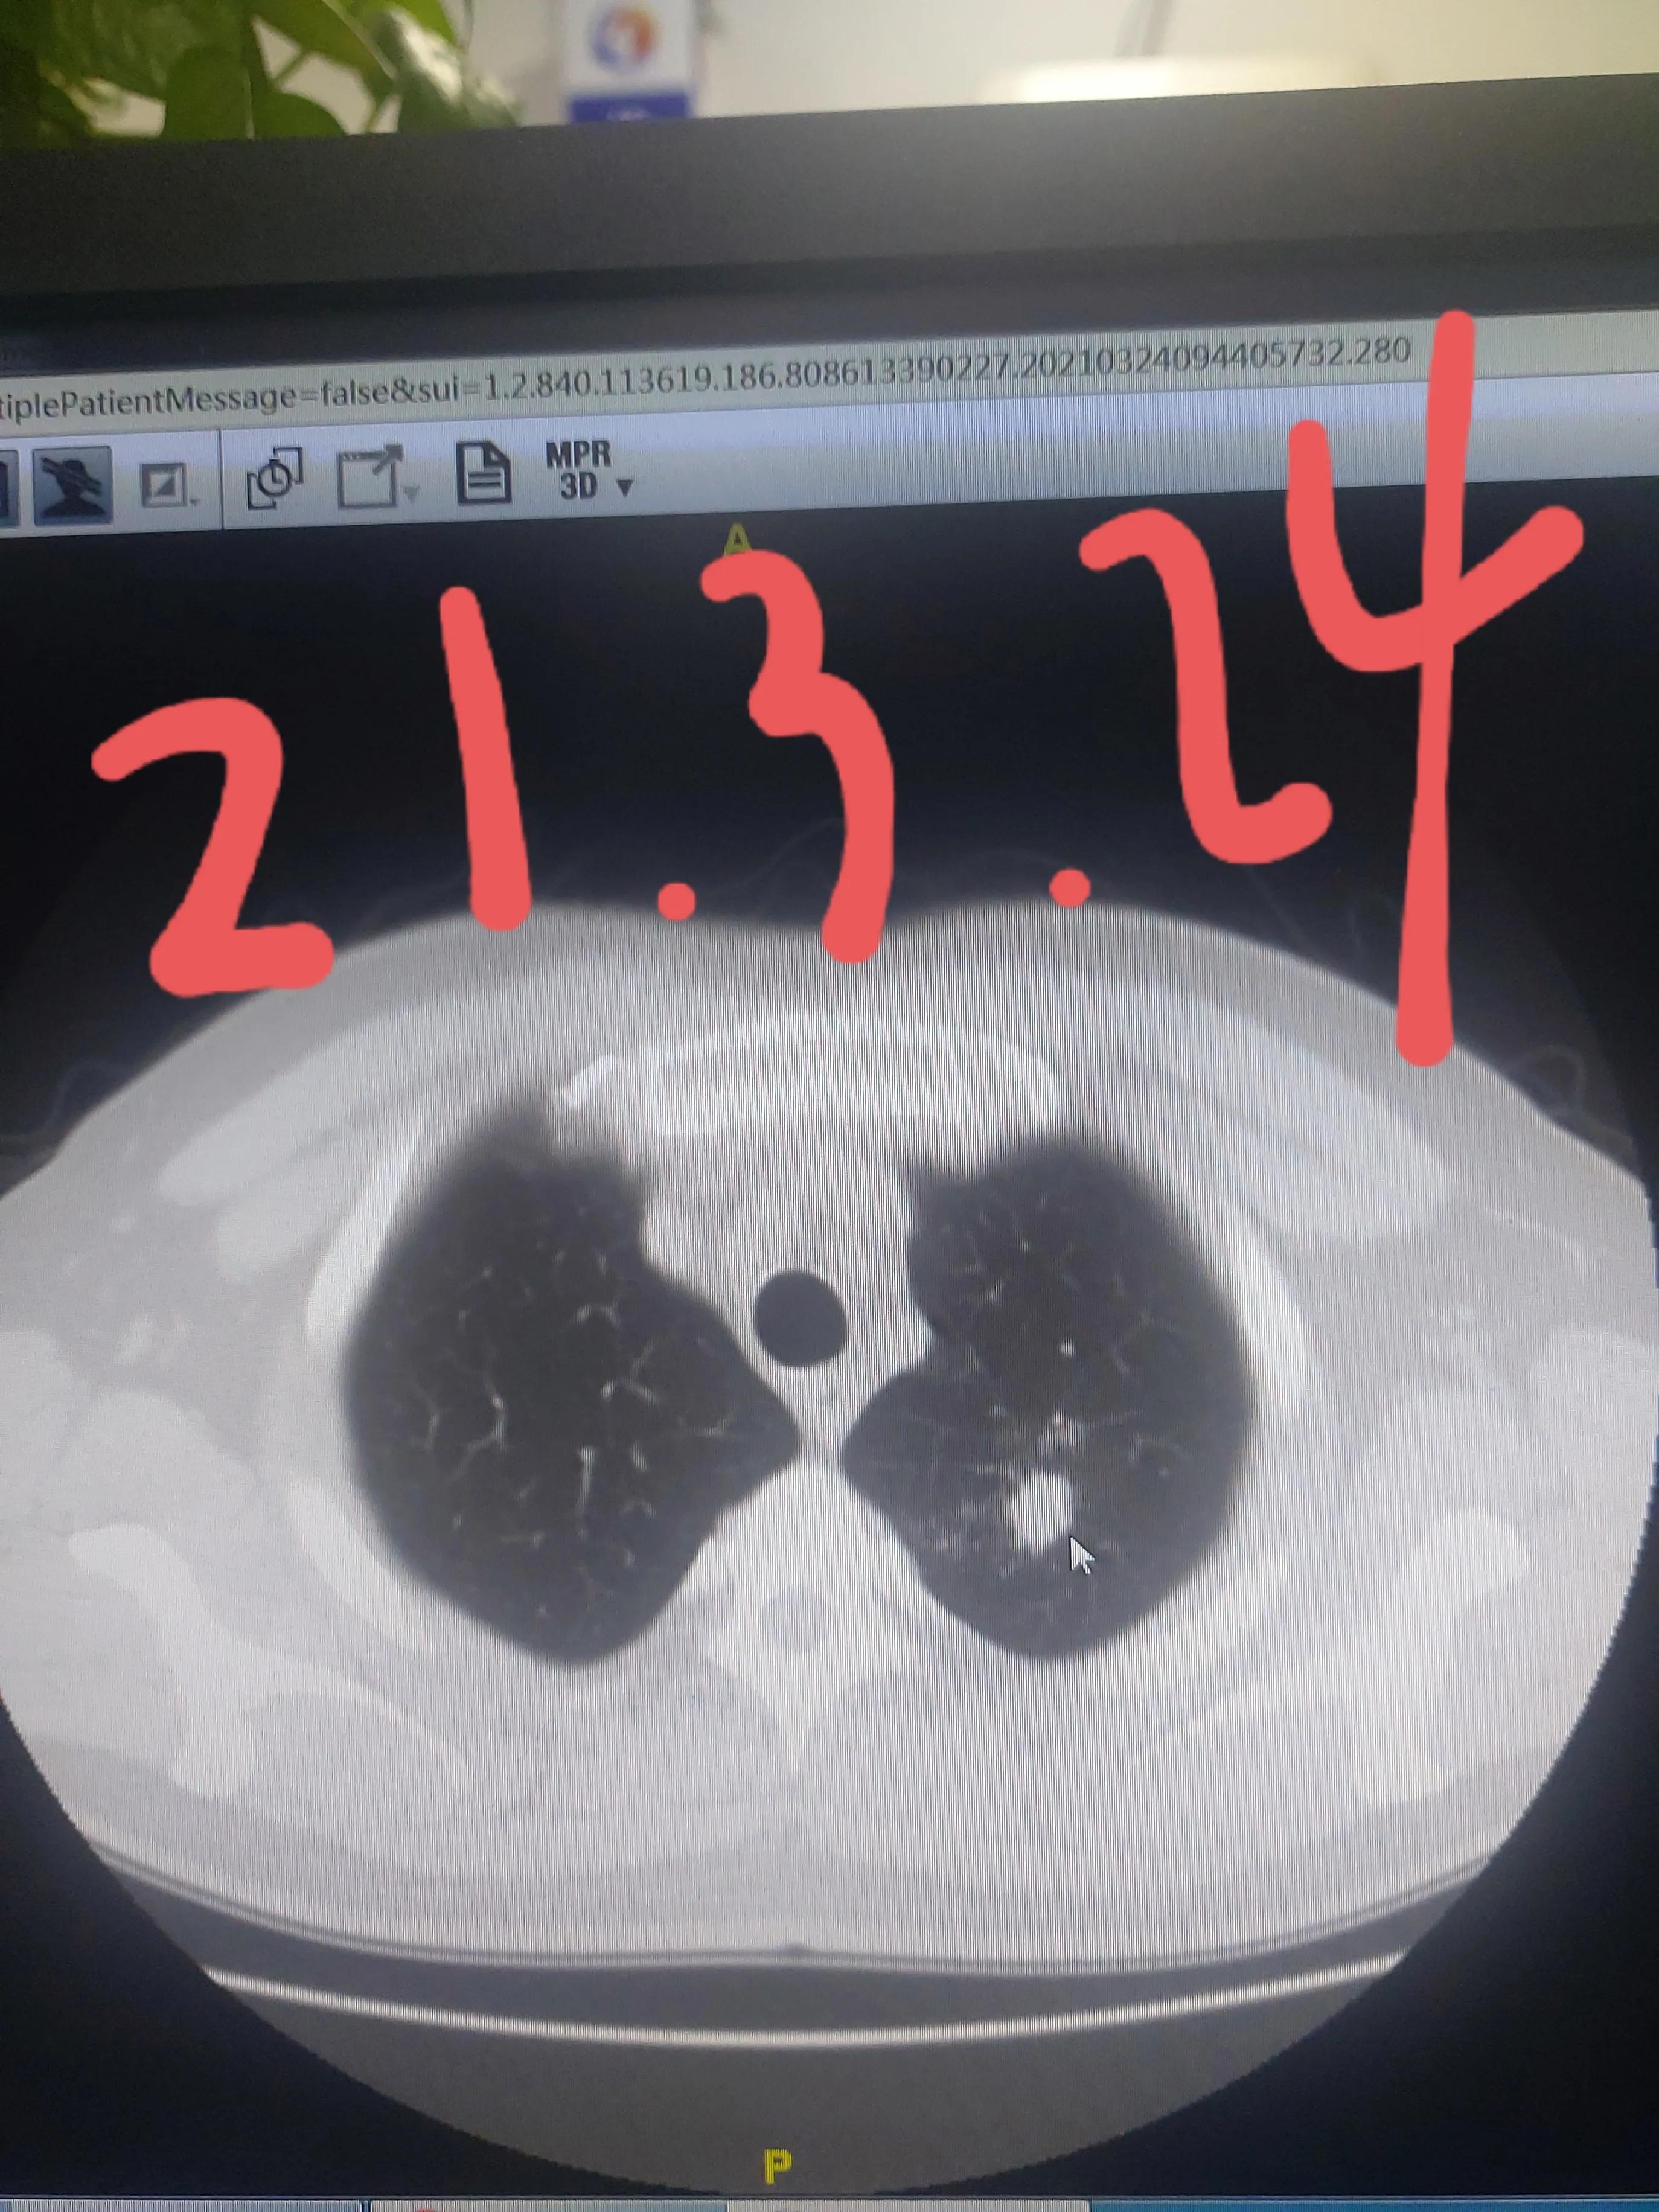

家属听从了我的安排,我给安排好了抗炎治疗,经过了一个疗程的治疗,距离上次一个月复查了胸部CT,果然这个结节比之前变小,并且出现了空洞,种种迹象表明这是一个良性的结节,我告诉他现在更不需要紧张了,目前不考虑是肺癌,定期再来复查就可以了,肯定不需要手术。